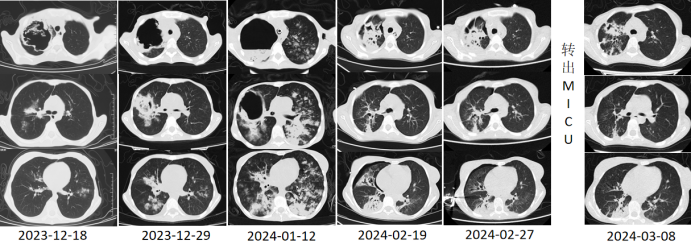

患者为18岁女性,因“全身水肿1月余,咯血27天,意识障碍4天”入院,既往有厌食症病史,BMI仅11.24 kg/m2(严重营养不良)。入院前1个月(2023年12月10日)无诱因出现眼睑、双足水肿,伴干咳、右侧肩背部疼痛,随后出现咯血;胸部CT提示双肺多发斑片影,右肺不规则空洞,壁厚不均匀(图1)。实验室检查显示感染指标显著升高:白细胞12.84×109/L,中性粒细胞11.48×109/L,快速C反应蛋白81 mg/L;血生化检查:谷丙转氨酶148 U/L,谷草转氨酶107 U/L,空腹血糖3.22 mmol/L,肌酐43 μmol/L。

图1 患者胸部CT(2023-12-29)